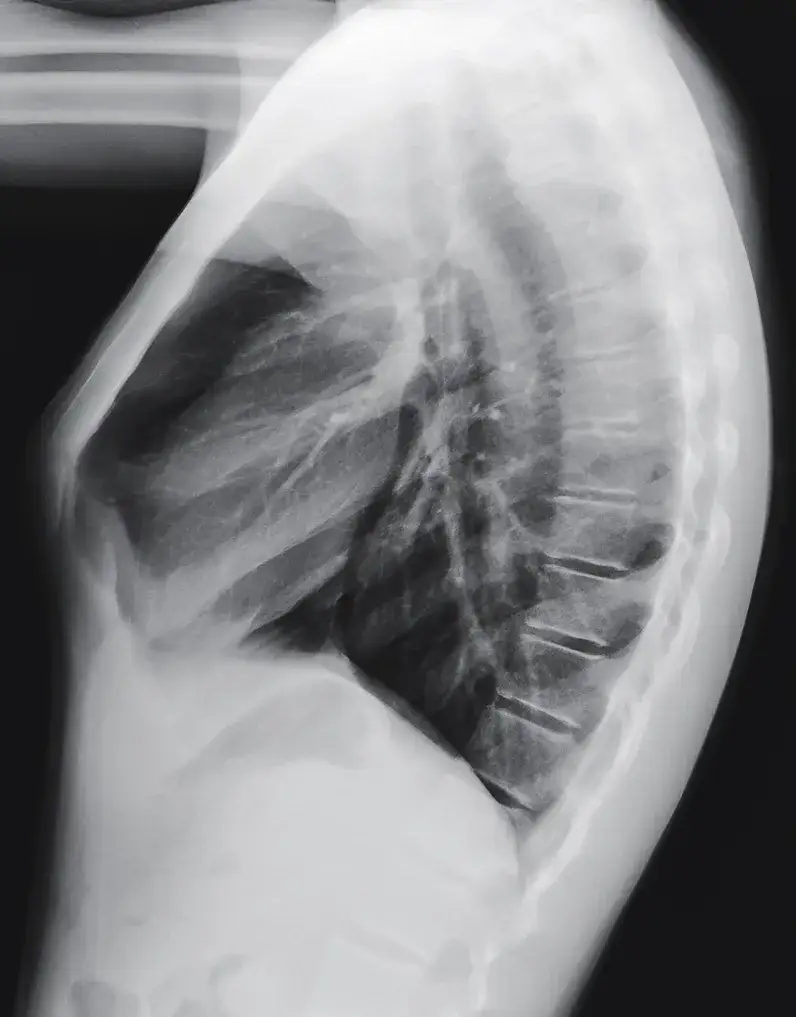

Diagnostyka schorzeń klatki piersiowej obejmuje szereg metod, od badania fizykalnego po zaawansowane techniki obrazowania. Lekarz może przeprowadzić osłuchiwanie, opukiwanie i badanie palpacyjne klatki piersiowej. W przypadku podejrzenia poważniejszych schorzeń, mogą być zlecone badania takie jak RTG, tomografia komputerowa czy rezonans magnetyczny.

- Radiografia klatki piersiowej

W diagnostyce radiologicznej często spotyka się określenia takie jak "radiografia pectus" lub "CT pectus", które odnoszą się odpowiednio do zdjęcia rentgenowskiego i tomografii komputerowej klatki piersiowej. W chirurgii, procedury takie jak "torakoskopia pectus" czy "rekonstrukcja pectus" są powszechnie stosowane w leczeniu schorzeń klatki piersiowej. Termin "pectus" pojawia się również w nazwach mięśni, na przykład "musculus pectoralis major" (mięsień piersiowy większy).